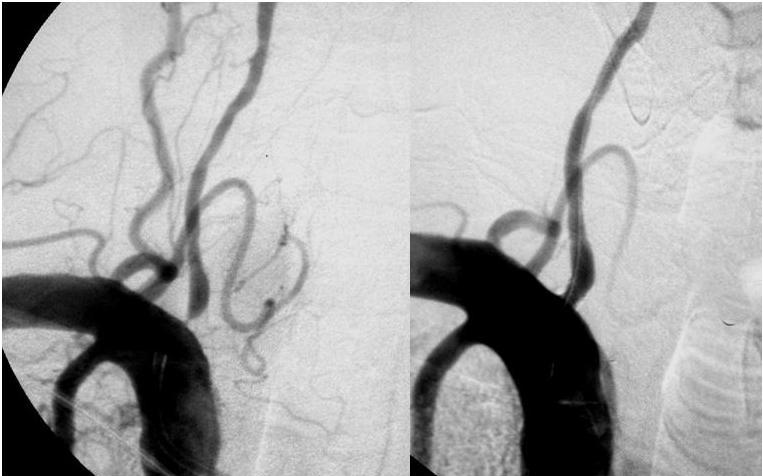

Lancet, 2 de noviembre 2017 En pacientes con angina tratada médicamente y estenosis coronaria severa, la ICP no aumentó el tiempo de ejercicio más que el efecto de un procedimiento de placebo. La eficacia de los procedimientos invasivos se puede evaluar con un control con placebo, como es estándar para la farmacoterapia.